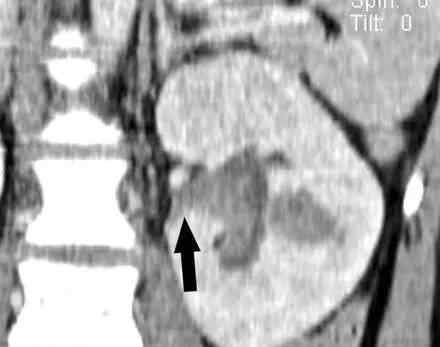

肾实质恶性肿瘤侵及肾窦

肾实质恶性肿瘤绝大多数呈球型硬块,朔性生长发育。侵及肾窦,挤压或侵害肾窦人体脂肪。具备象征性的是肾细胞癌和良好的多房性囊性肾瘤。

肾细胞癌,是最普遍的肾实质恶性肿瘤,绝大多数肾细胞癌朔性生长发育一般侵及肾窦。造成 部分肾盂积水和肾盏挪动。侵及肾窦的临床表现取决于和移形细胞癌的差别,及其恶性肿瘤的分期付款对普外医治的危害。肾细胞癌有向肾静脉血管延及的发展趋势。肾一部分摘除术适用 3厘米,未侵犯到肾窦人体脂肪,肾周人体脂肪和肾脏功能搜集系统软件,尤其是在这些肾脏功能衰减系数,孤立肾,双侧肾脏功能肿瘤的病人。侵犯到肾窦人体脂肪代表着肾一部分摘除术不可以取得成功的,彻底的 摘除恶性肿瘤。三维 CT和MRI可以显示信息肾脏肿瘤的部位,和搜集系统软件,静脉血管系统软件的关联。